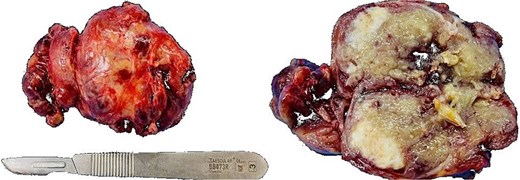

An exploratory surgery was performed, during which a well-encapsulated retroperitoneal mass was identified near the pancreas. The mass was completely removed with preservation of surrounding structures (Fig. 3). Gross examination showed a 60 × 45 × 35 mm yellow–gray encapsulated mass with scattered calcified foci (Fig. 4).

Gross specimen showing a 60 × 45 × 35 mm encapsulated, yellow–gray mass with scattered calcifications.